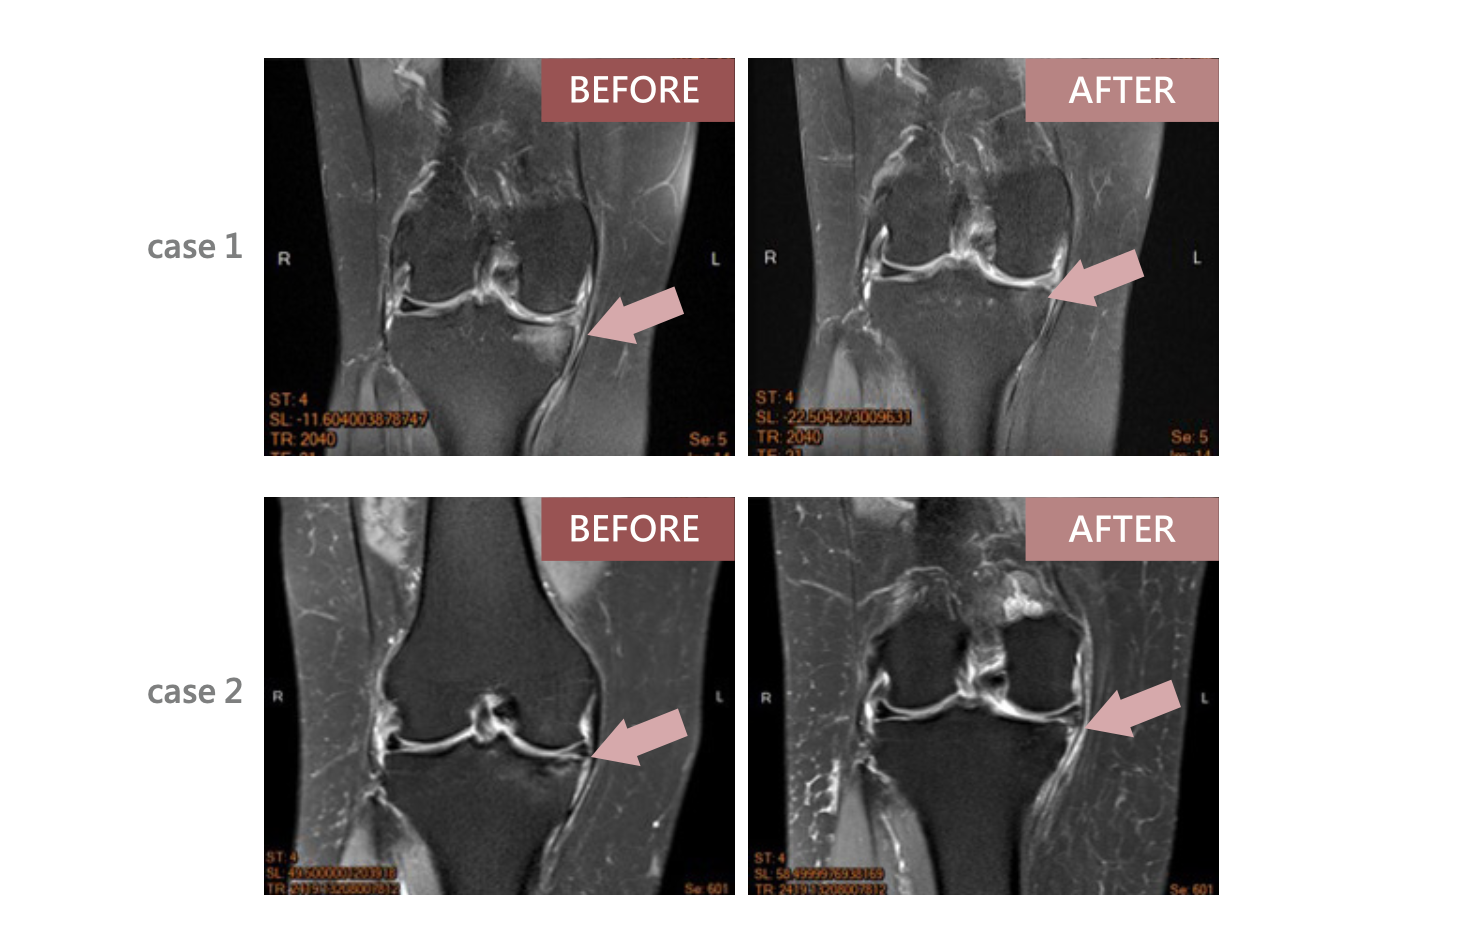

退化性關節炎臨床成果

臨床成果頁顯示,AI Cells 可有效改善退化性關節炎患者的疼痛,並提升運動功能。圖中以 KOOS Analysis 呈現疼痛、症狀、日常活動、運動能力與生活品質等指標,於追蹤 12 個月與 24 個月時皆可見改善趨勢。

此外,關節腔內注射 AI Cells 治療後,也可見軟骨下骨水腫症狀減輕的影像案例,顯示其在退化性關節炎臨床應用上具有參考價值。